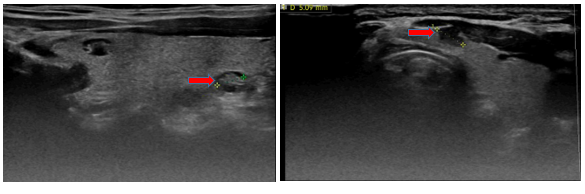

- Siêu âm tuyến giáp (trước mổ): Hình ảnh nhân giảm âm thùy phải và eo tuyến giáp khoảng 5mm (TIRADS 4). Nhân hỗn hợp âm thùy phải tuyến giáp (TIRADS 3). Dưới cằm lệch phải có vài hạch, kích thước lớn nhất 7mm, cấu trúc bình thường.

Hình 2: Hình ảnh siêu âm tuyến giáp và vùng cổ có nhân giảm âm thùy phải và eo tuyến giáp khoảng 5mm (TIRADS 4), (mũi tên đỏ)